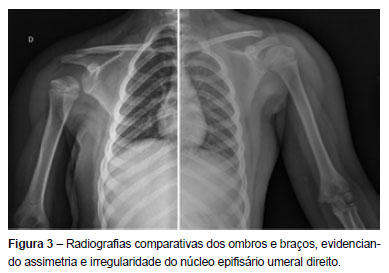

Atualmente, aos oito anos de idade, apresenta discreta diminuição da rotação interna do ombro direito e encurtamento do membro superior direito de cerca de 2.5 cm (Figura 2). As mobilidades das ancas são simétricas e não há dismetria dos membros inferiores.

O diagnóstico tardio de artrite séptica do ombro pode lesar a fise e comprometer o crescimento do úmero proximal, com consequente encurtamento e deformidade do membro superior, como sucedeu no caso descrito (Figuras 2 e 3).(7)